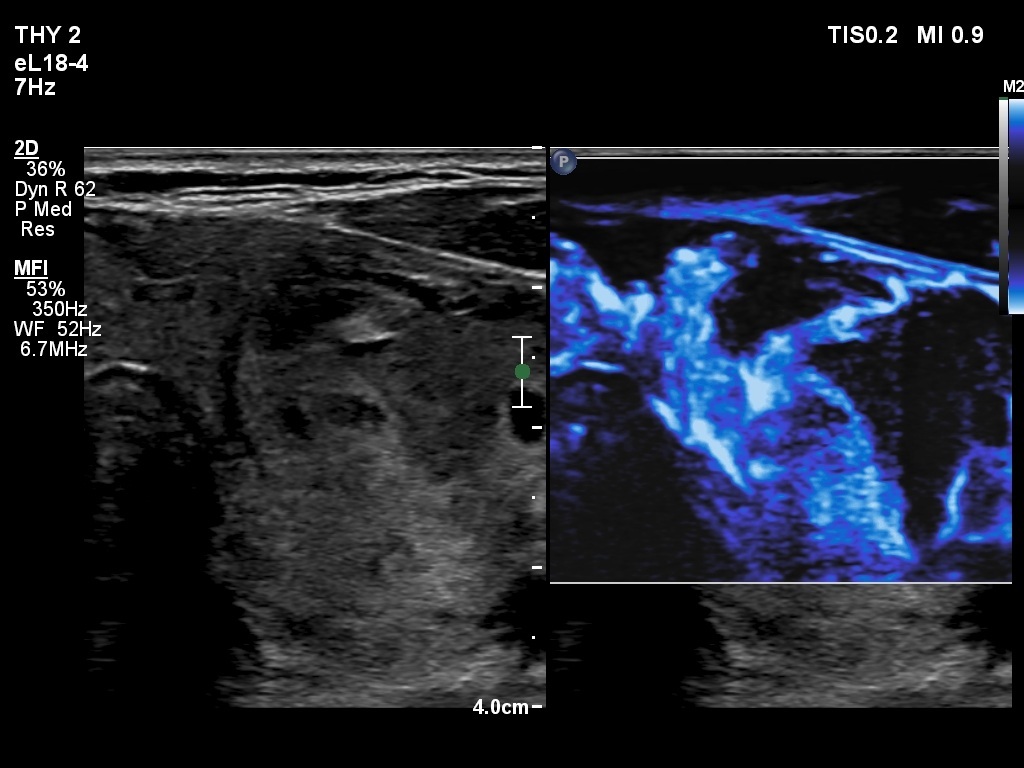

The composition of the nodule - case 1497 (ultrasonographic picture 12)

Right lobe, longitudinal scan

Left lobe, transverse scan, microflow imaging - after the removal of 6 mL brown fluid.